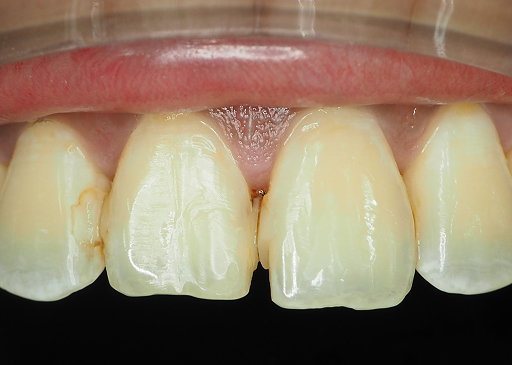

Trigger: Cold/hot or sugary food

Cause: Tooth cavity (beyond Enamel) or loose filling

Trigger: Cold/hot or acidic food

Cause: Exposed root or eroded enamel

For: Sensitive tooth and safeguard against decay

For: Sensitive tooth

Significant aesthetic improvement for anterior teeth